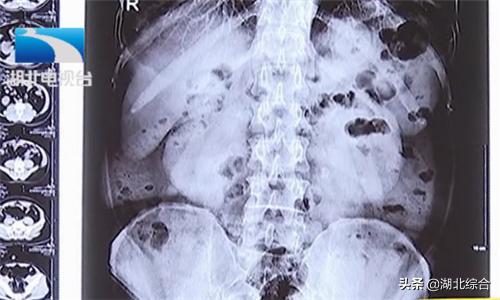

武汉京都结石医院泌尿结石医生张辉解释:“双肾都有积水,主要是右边积水比较重,大概是4公分左右,左边的积水是2公分左右,结石的大小大概都是在2公分左右。”积水严重,且左右两侧输尿管被结石和息肉包裹。如不及时处理结石梗阻问题,随时有危及生命的风险。